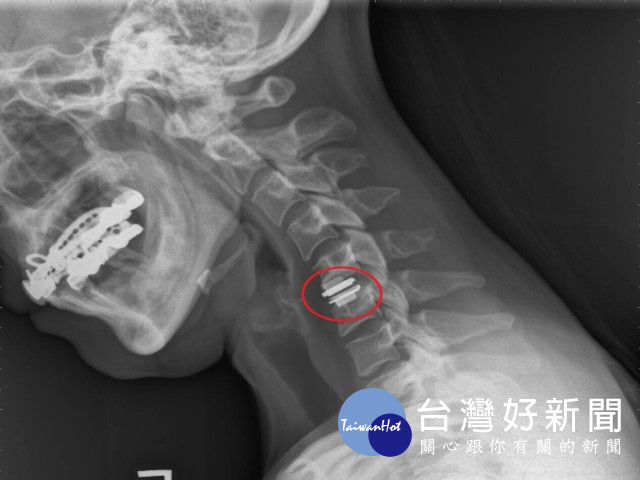

62歲榮民頸椎病變,長年頸部疼痛及手麻痛感,最期症狀加劇,手無力、無法躺平。經大甲李綜合醫院院長暨神經外科權威醫師張迪生檢查後,確認頸椎病變,建議進行「頸椎人工椎間盤置換」,施以「微創腰椎手術」,隔天即可自由活動,亦不需戴頸圈,讓老榮民終於能睡得一好覺。

醫師張迪生表示,腰椎退化是老年人常見的病症之一,微創與傳統腰椎手術的目的,都是為了減輕神經的壓迫與椎體穩定和關節面平衡,此兩種手術在文獻研究與臨床下,其神經減壓與骨融合的術後結果是相同的,差別在於使用的手術方法不同。傳統的脊椎手術傷口較大,容易造成手術部位的正常結構組織傷害,術後恢復期長,且容易產生後遺症。

相反的,「微創腰椎手術」的安全性相對增高,因為傷口小手術創傷低,故手術出血量也會偏少,且不需切開肌肉,可盡量保留肌肉功能,減少對背部肌肉和軟組織的傷害,一般傷口在一公分左右,術後疼痛感比起開放性手術少了許多,病患術後恢復良好,隔日即可下床行走及出院,與傳統手術相比其術後產生之後遺症較少。